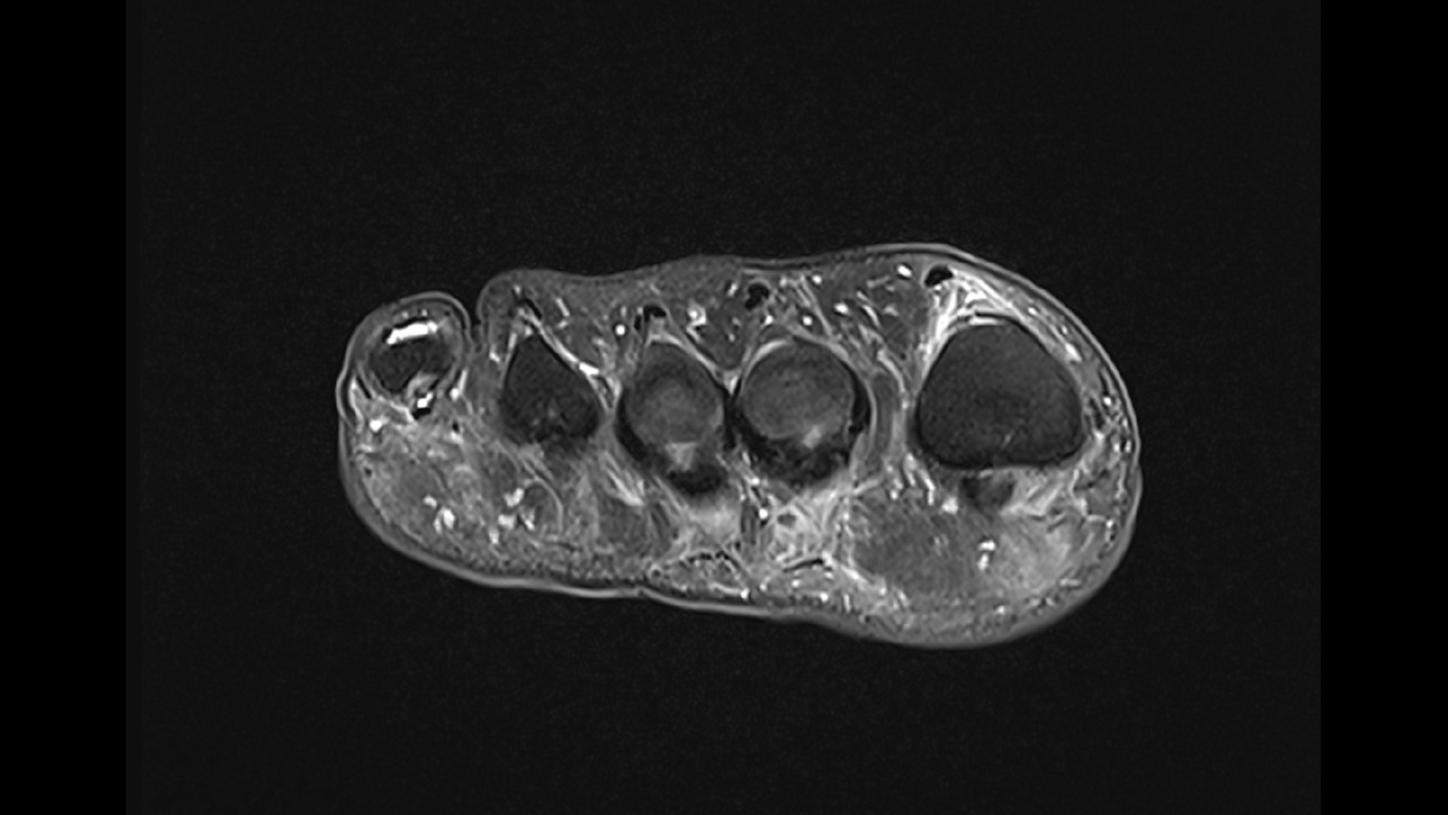

Morton Neuroma Mri

Morton Neuroma Mri / It's also called an intermetatarsal neuroma because it's located in the ball of the foot between your.